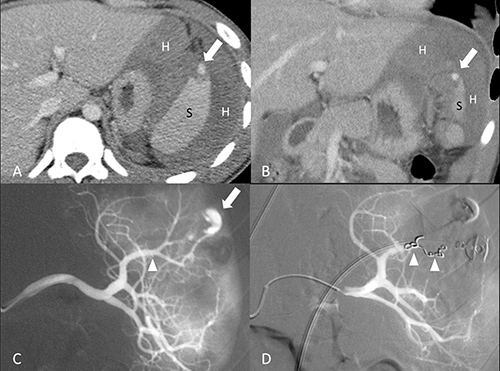

Figure 2: 18-year-old male of grade II splenic injury underwent distal transcatheter arterial embolization. (A, B) Contrast-enhanced axial and coronal CT at portal venous phase shows a pseudoaneurysm (arrow) at the lacerated spleen (S) surrounded by hemoperitoneum (H). (C) Selective angiography confirms the CT finding of a pseudoaneurysm (arrow) and identifies the feeding branch artery (arrowhead). (D) Angiography after a successful distal embolization shows deployment of metallic coils (arrowheads) at the branch artery and obliteration of pseudoaneurysm.